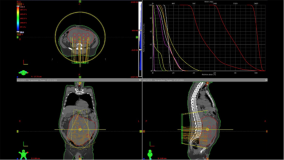

The Human Health Campus is an educational and resource website for health professionals in radiation medicine (nuclear medicine, diagnostic imaging, radiation oncology and medical radiation physics) and nutrition.

The Campus is one of the tools used by the IAEA Division of Human Health to achieve its mission, which is to "Enhance the Capabilities in Member States to Address Needs Related to the Prevention, Diagnosis and Treatment of Health Problems through the Application of Nuclear Techniques". The Division aims at becoming a "Learning Organization" in ways that foster a collaborative learning environment among all participants.

| Data Type | Training Multimedia |

| Keywords | Human Health Campus; Cancer; Human Health; Nuclear Medicine; Diagnostic Imaging; Applied Radiation Biology; Radiotherapy; Dosimetry; Medical; Training material |